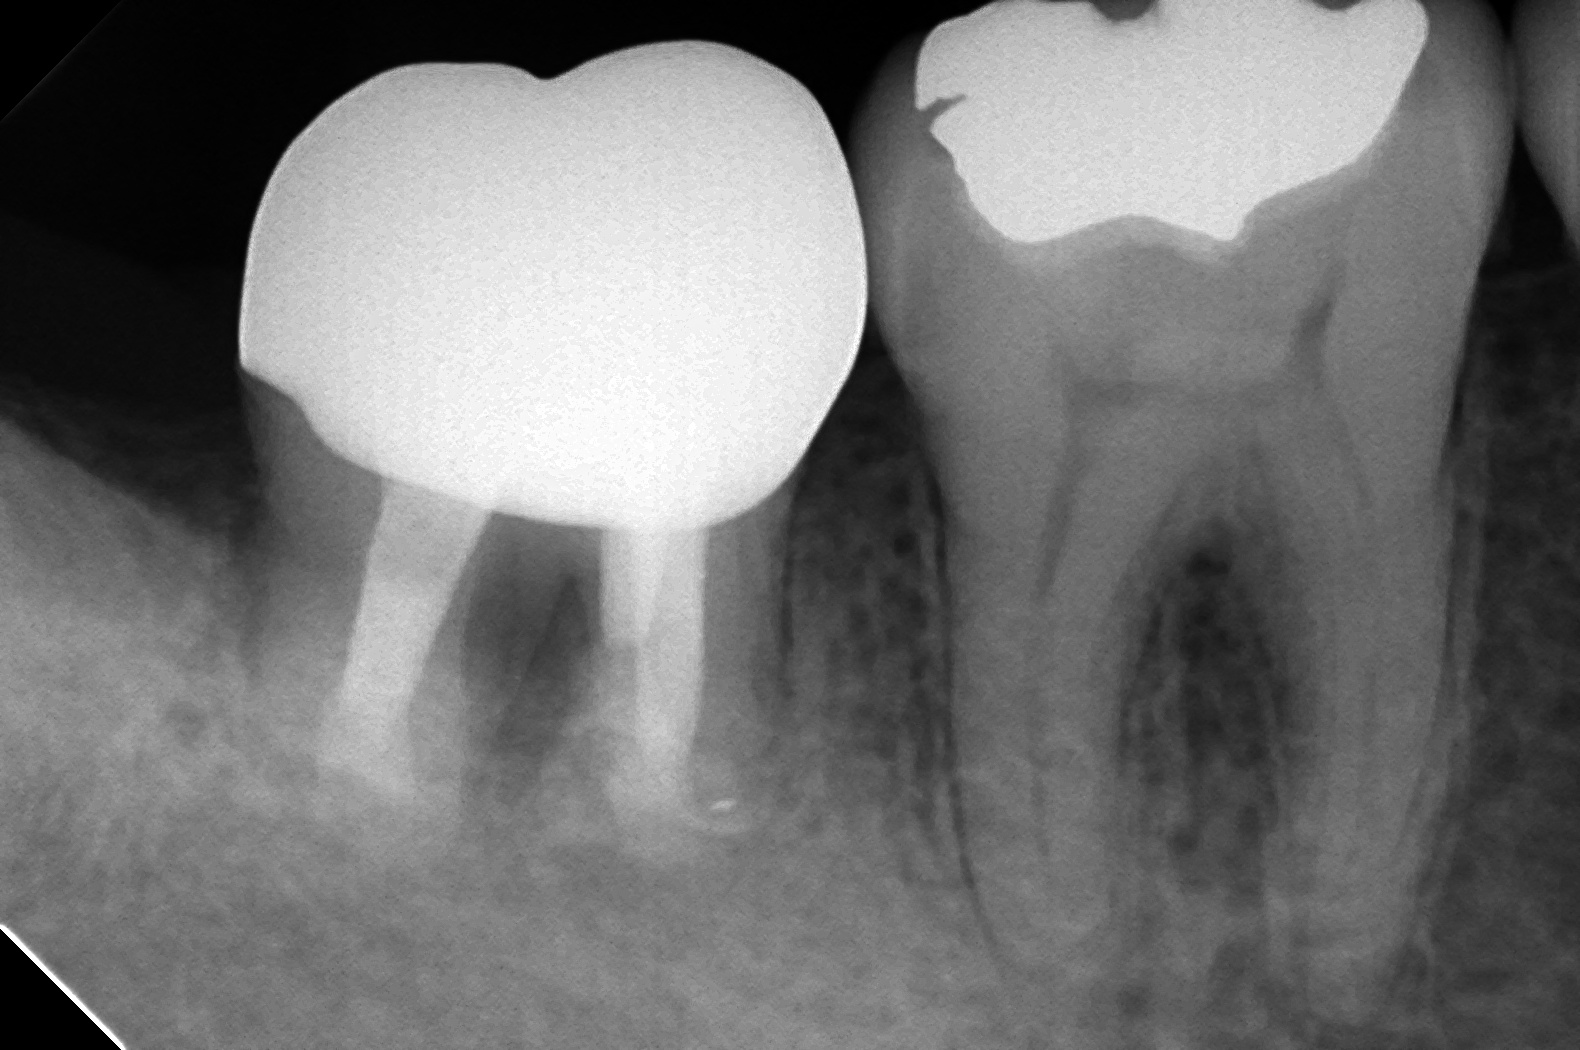

PBN97_140605115041(調整後)初診時

7番の根尖に大きな病変を認めます。

噛んだときのお痛みが主訴で来院されました。

DB9747_140617125230(調整後)根充後

自分で言うのもあれですが、ホントに綺麗に時間かけてやったので治らないわけがないと思ってました。

根充の質も悪くありません。